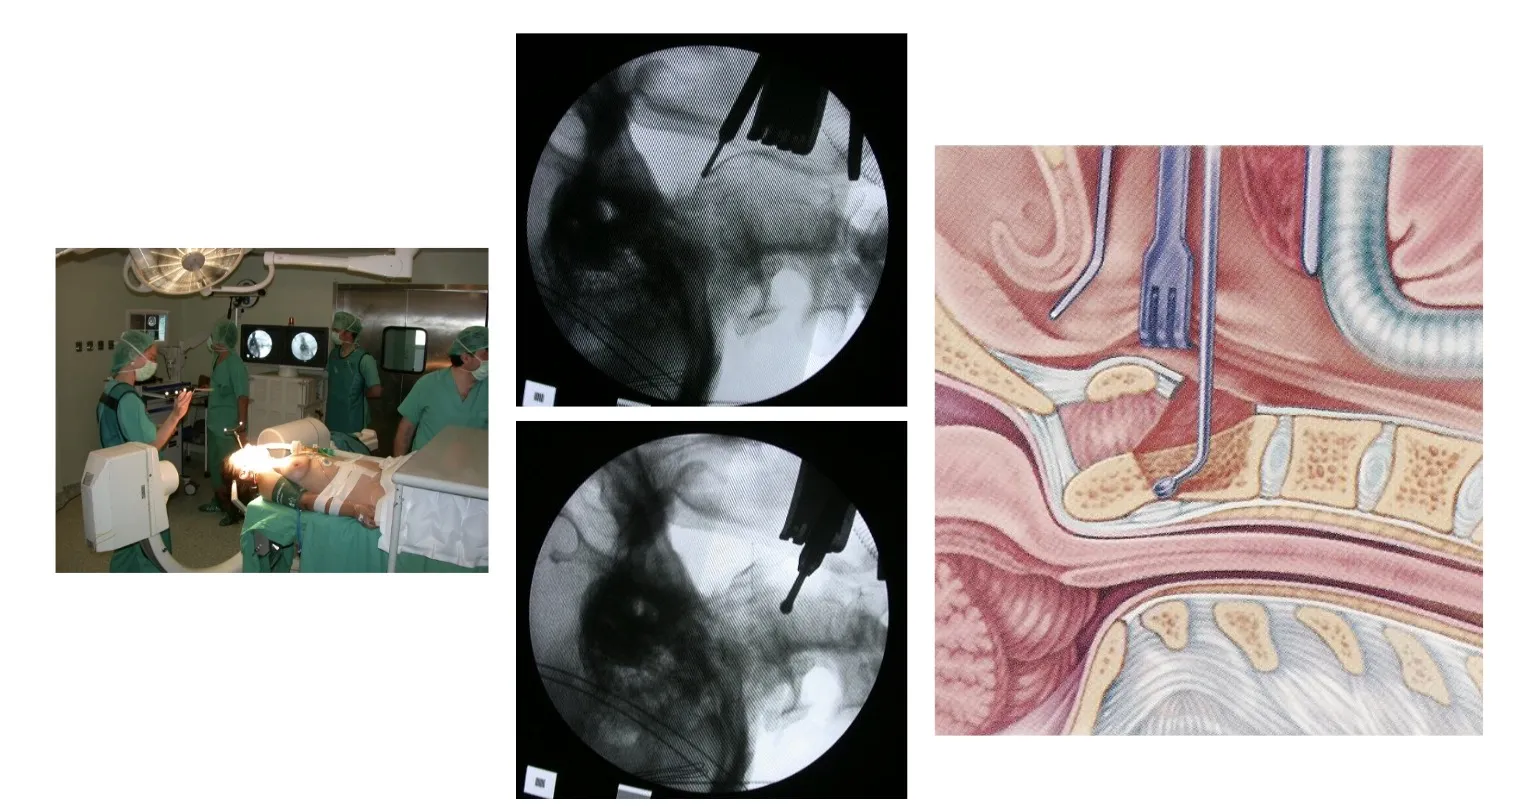

En la figura se muestra un ejemplo de abordaje transoral, es decir, realizado a través de la boca, para acceder a un tumor localizado en la segunda vértebra cervical. Este tipo de intervención permite alcanzar directamente la lesión situada en la parte anterior de la columna cervical alta, garantizando un acceso preciso y un control adecuado del campo quirúrgico.

En estos casos, es posible utilizar sistemas de fijación que permiten anclar el cráneo a la columna cervical, con el fin de mantener la estabilidad y evitar el colapso producido por la invasión tumoral de la vértebra afectada. Estas fijaciones, realizadas mediante placas, tornillos y barras especialmente diseñadas, aseguran la continuidad estructural entre el cráneo y la columna, garantizando la correcta alineación y protección de las estructuras neurológicas.

La mesa de Jackson es quizá uno de los elementos más importantes de esta tecnología. Además de permitir una colocación óptima del paciente, su característica fundamental es que está fabricada en fibra de carbono, lo que la hace completamente radiotransparente. A diferencia de las mesas convencionales, no tiene una columna de soporte en el centro —precisamente la zona donde necesitamos operar—, sino que el apoyo se realiza por los extremos. Esto facilita el acceso del arco de rayos X desde cualquier ángulo durante la intervención. La mesa puede soportar hasta 200 kg, lo que permite intervenir con seguridad incluso a pacientes con obesidad, manteniendo siempre una visión radiológica perfecta del campo quirúrgico. En operaciones de alta complejidad, en las que el cirujano debe dominar distintos niveles vertebrales a lo largo de toda la columna, esta mesa ofrece una maniobrabilidad extraordinaria. Además, su diseño favorece una correcta posición del paciente, mejorando la ventilación pulmonar, la circulación y la seguridad anestésica. En definitiva, se trata de un equipamiento concebido específicamente para la cirugía de columna vertebral.

Una vez que el paciente se encuentra en posición quirúrgica —habitualmente en decúbito prono—, se cubre con los paños estériles y el sistema radiológico puede girar libremente alrededor de su cuerpo, permitiendo visualizar cualquier parte de la columna, desde la región cervical hasta la sacra. El equipo de rayos se sitúa junto al campo operatorio, de modo que puede utilizarse en cualquier momento durante la intervención sin interrumpir el trabajo del cirujano, que opera con la ayuda del microscopio.